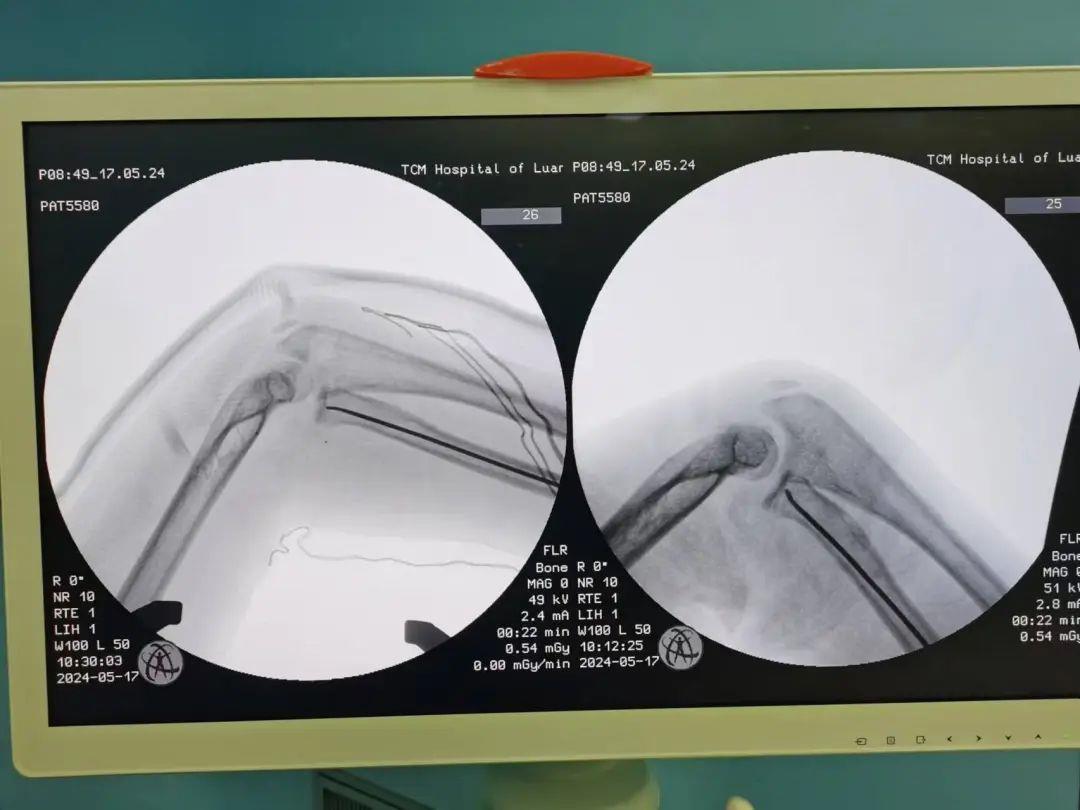

42岁的王女士,因不慎跌倒致髋部疼痛活动受限来骨科就诊。诊断为左侧股骨颈骨折,骨科团队对患者病情进行综合评估,提出创新快速康复理念,考虑采用一种新型股骨颈内固定系统—股骨颈动力交叉钉系(FNS)。整个手术过程十分顺利,用时约2小时。手术切口仅5cm,术后影像学检查,骨折对位对线良好,内固定稳固可靠,术后当天患者疼痛明显缓解,可在床上进行患肢功能锻炼,患者及家属对此次治疗非常满意。

左图为我科开展的FNS股骨颈动力交叉固定系统固定股骨颈骨折

右图为市内常规开展的空心钉内固定术固定股骨颈骨折